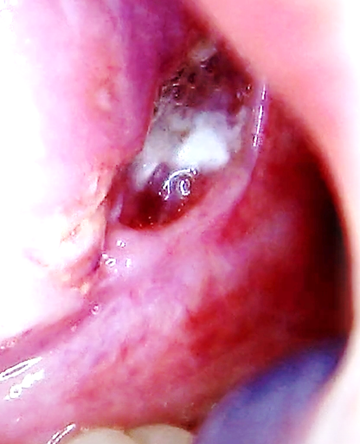

▶ 설염과 설암

혀에 생기는 구내염이 설염이고 암을 설암이라고 한다.

설암인데 구내염인줄 알고 장시간 방치하는 경우가 많다.

한 달 이상 같은 자리에 지속적으로 증상이 있다면 병원에서 진료를 받는 것을 추천한다.